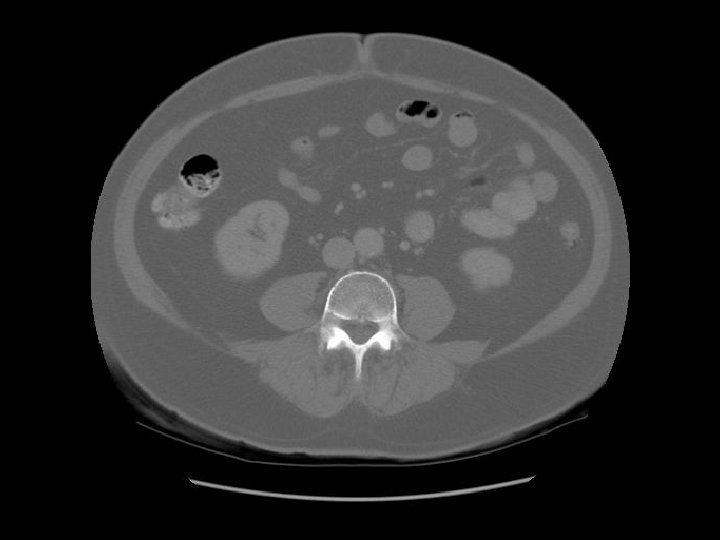

Transverse colon Ileum

Descending colon Right

Ascending colon Right colon with fecal material.

Psoas